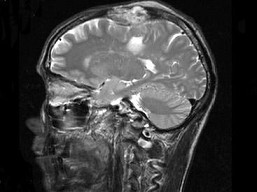

男,63岁,反复抽搐30余年加重伴左侧肢体活动不利活1月余,PE:右顶部约4cm×5cm大小隆起包块质硬,不能活动,右上下肢肌力Ⅴ,左上下肢肌力Ⅳ+,根据所提供图像,最可能的诊断为()

A.右顶骨(付脊索瘤)或称为肌上皮瘤

B.右顶骨转移瘤

C.右顶骨骨瘤

D.右顶骨血管瘤

E.右顶骨胆脂瘤

[单选题]男,63岁,反复抽搐30余年加重伴左侧肢体活动不利活1月余,PE:右顶部约4cm×5cm大小隆起包块质硬,不能活动,右上下肢肌力Ⅴ,左上下肢肌力Ⅳ+,根据所提供图像,最可能的诊断为()A . 右顶骨(付脊索瘤)或称为肌上皮瘤B . 右顶骨转移瘤C . 右顶骨骨瘤D . 右顶骨血管瘤E . 右顶骨胆脂瘤